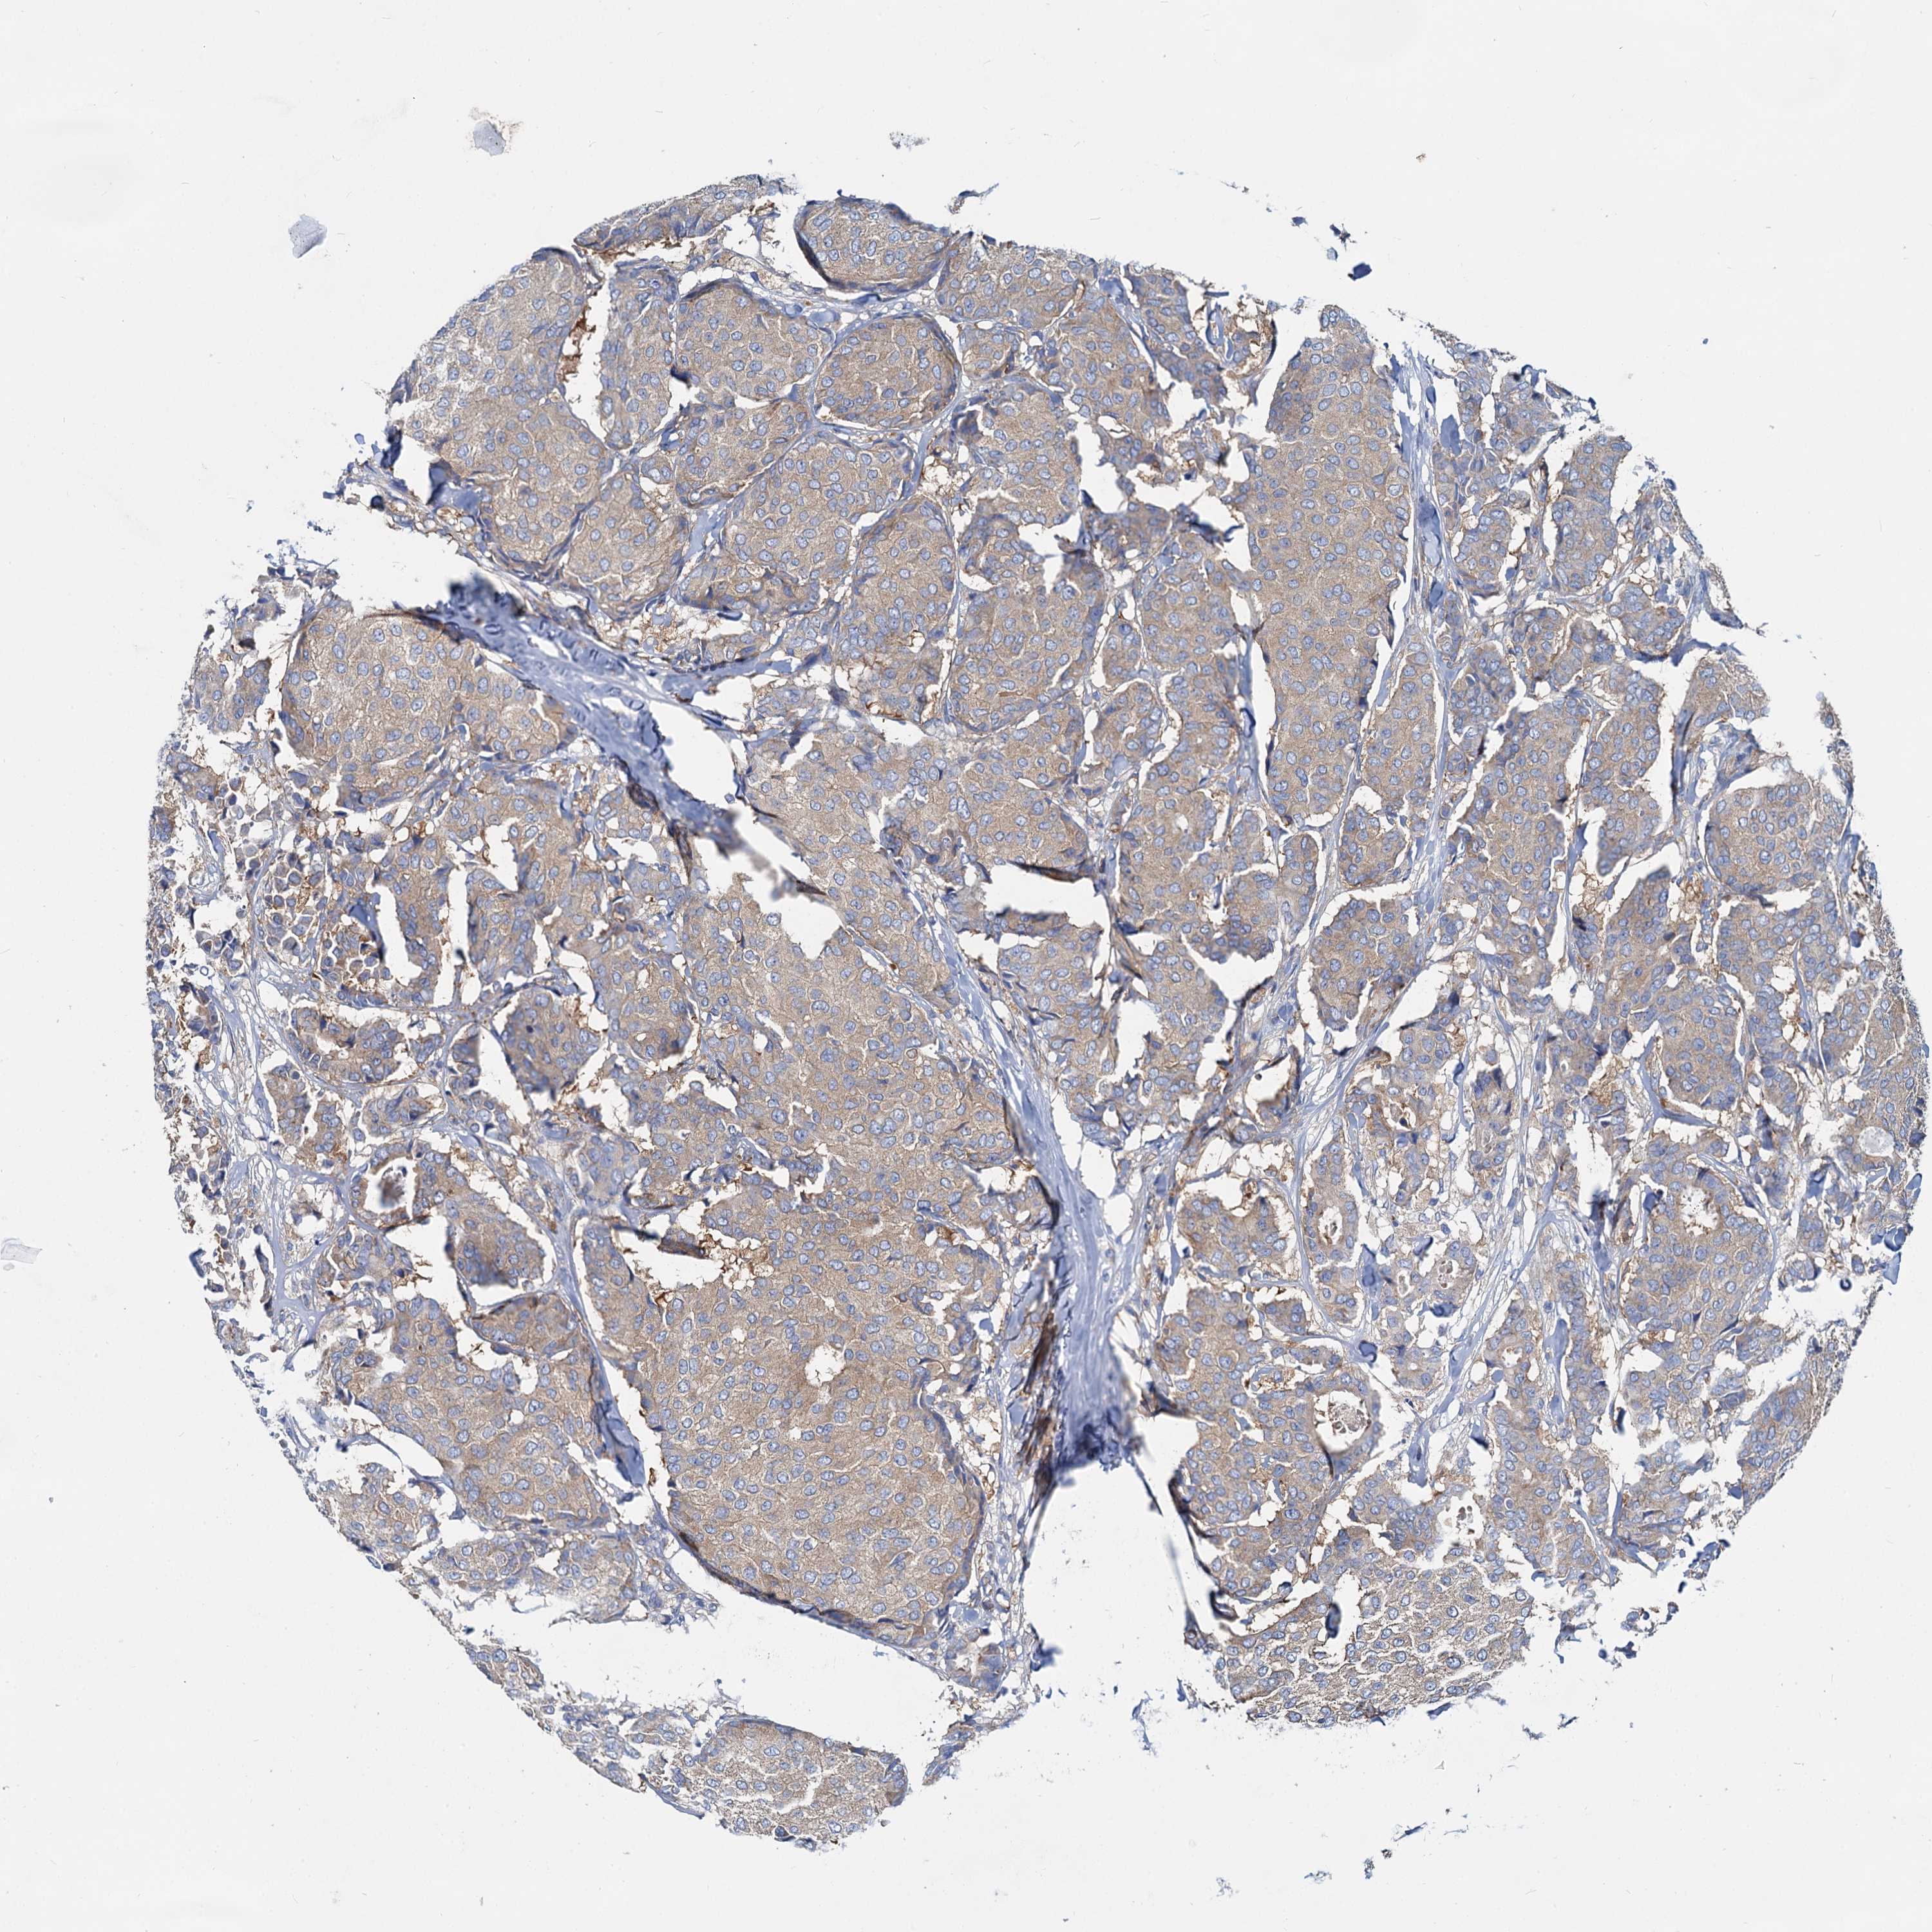

CANCER BREAST CANCER Show tissue menu

BRCA TCGA BRCA VALIDATION PROTEIN EXPRESSION